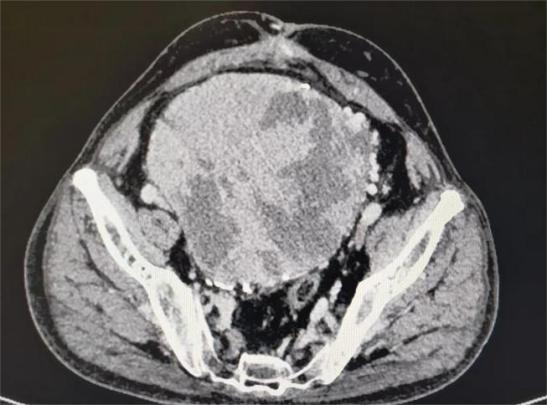

术前影像学:占位范围广、周围比邻多支神经血管

王先生住院后,医生们查阅他的各种影像资料后,均倒吸了一口凉气。王先生的肿瘤直径已达20多厘米,占据整个盆腔、周边紧压大血管和盆腔器官,手术切除犹如“虎口拔牙”,难度极大、风险极高,甚至可能引发大出血后死于手术台上。尽管王先生的家属早有心里准备,听完医生介绍病情后,看着饱受病痛折磨的父亲,家属与本人商量后,还是希望苏州大学附属第四医院的医生们能帮忙搏一搏。

今年59岁的王先生来自镇江,平素体格强壮、性情豪爽,本是家中的顶梁柱。但本来和谐幸福的家庭被王先生两年前的一次晕倒打破。2022年初,王先生因不明原因出现心慌、盗汗,随后陷入昏迷状态,被家人紧急送医院救治,检查发现严重低血糖,血糖最低只有1mmol/L!经补充糖水后好转。此后他又出现严重低血糖,抢救多次。为了找到低血糖昏迷的原因,多次来往医院检查,最终CT检查发现盆腔有个大肉瘤,足足有小孩子头那么大!经穿刺活检提示为低度恶性的梭形细胞瘤,而且具有内分泌功能,能够分泌胰岛素。医生推断该肉瘤是引起王先生低血糖昏迷的罪魁祸首。诊断书犹如晴天霹雳,让原本充满欢笑的家庭阴云密布。